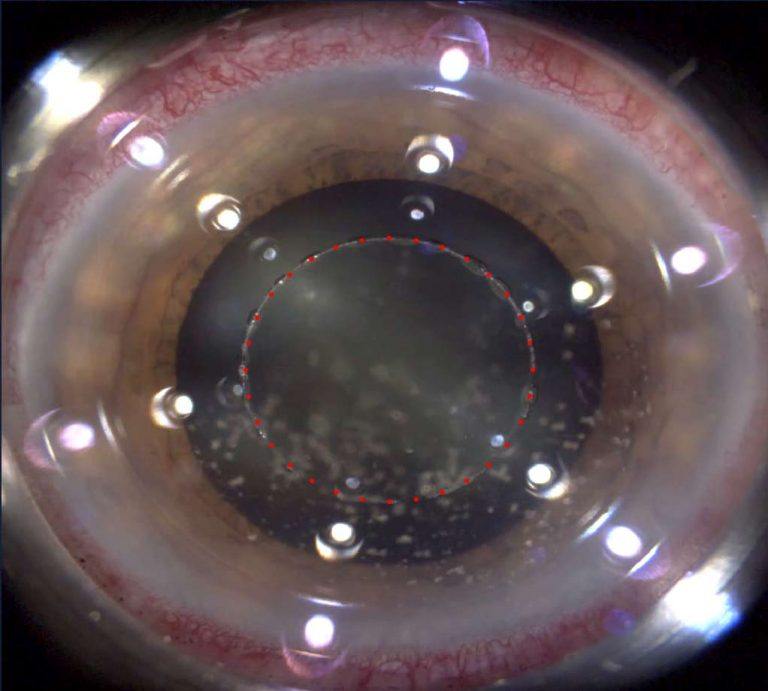

Hornhäute mit Keratokonus sind in der Regel dünner als normale Hornhäute. Sofern sie aber nicht extrem dünn sind, sollte dies keinen Einfluss auf die technischen Schwierigkeiten des Eingriffs haben. Bei ELZA können wir die Option anbieten, die Kataraktchirurgie mit einem Femtosekundenlaser zu unterstützen. Dabei macht der Laser superpräzise Schnitte in die Hornhaut, führt eine Kapsulotomie durch und fragmentiert die Linse vor, um den gesamten Eingriff so sicher und sanft wie möglich zu gestalten. Dieser Ansatz sollte in Betracht gezogen werden, wenn Augen mit sehr dünner Keratokonus-Hornhaut eine Kataraktoperation erfordern.